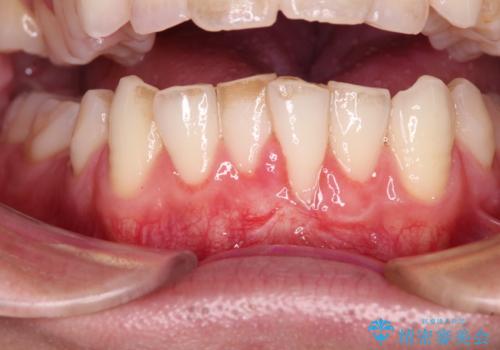

1回目の処置で多少は被覆され歯肉が厚くなりましたが、十分とは言えなかったため、2回目の処置を行いました。

2回目の処置後には十分な厚みと、十分な被覆量を獲得することができました。